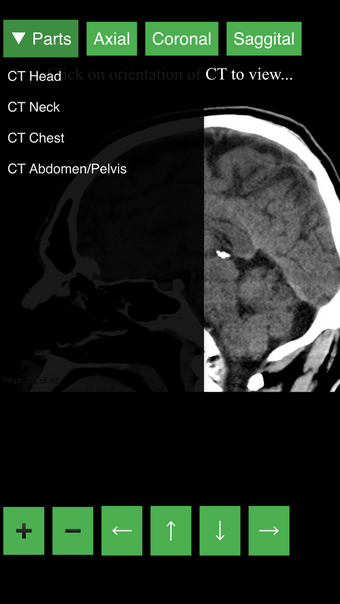

Radyoloji BT Görüntüleyicisi, doktorlar, tıp öğrencileri, radyoloji teknisyenleri ve diğer sağlık profesyonellerinin insan vücudu ve anatomisi hakkında daha fazla bilgi edinmelerine yardımcı olan faydalı bir araçtır. Uygulama, en önemli insan vücut parçalarının detaylı kesit çizimlerini içerir. Ayrıca, anatomiyi daha iyi görmek için görüntü etrafında döndürme, yakınlaştırma ve kamera hareket ettirme imkanı sunan etkileşimli bir 3D model içerir.

İnsan vücudu hakkında daha fazla bilgi edinmenize yardımcı olacak bir araç arıyorsanız, Radyoloji BT Görüntüleyicisi harika bir seçimdir. Detaylı çizimler ve etkileşimli bir 3D model içerir.